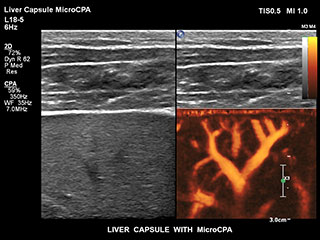

Bisher war die Erfassung von Flussdaten bei kleinen Gefäßstrukturen mit niedriger Flussrate schwierig. Die neue EPIQ Funktion MicroCPA bietet eine schnelle und einfache Darstellung von Mikrozirkulation mit niedriger Geschwindigkeit und ermöglicht eine hohe Diagnosesicherheit bei der Beurteilung der Organperfusion oder von kleinen Gefäßbetten.